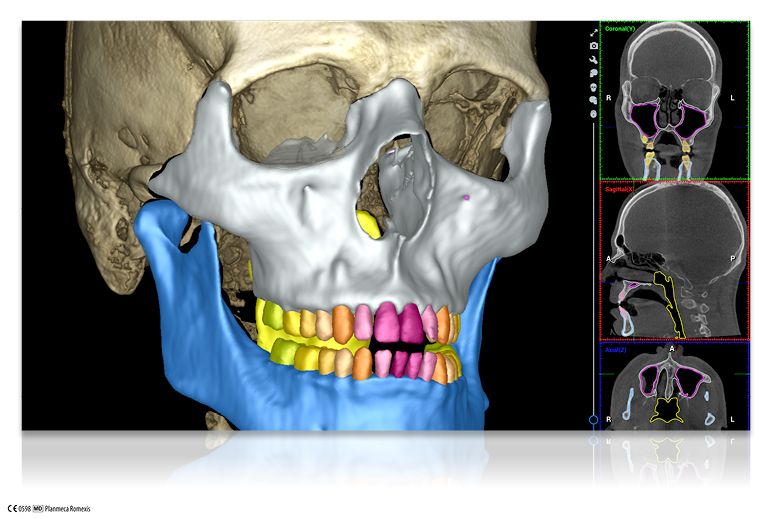

Planmeca Romexis® Smart are artificial intelligence (AI) tools for its Planmeca Romexis software platform. The feature allows the segmentation and recognition of anatomies, such as teeth, nerves, jaws, airways, and sinuses. This enables easier and faster use of the software and excellent visualization of the case for patient education. With the help of AI, CBCT images and intraoral scans are automatically mapped. Thanks to the automatic tooth number recognition, a CBCT volume can be easily navigated just by clicking on the tooth number in the tooth chart, and the software centers all views on the tooth of interest.